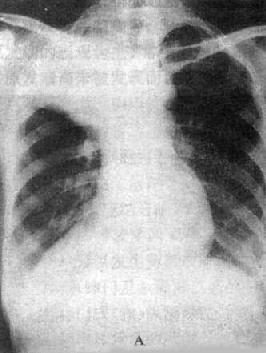

图3-1-28 右上叶支气管肺癌(中心型)

A.后前位B.前后位体层像右上叶密度均匀增高,下缘清楚、上突,

与肺门肿块影形成似横置S状。体层像示肿块突入右支气管腔内